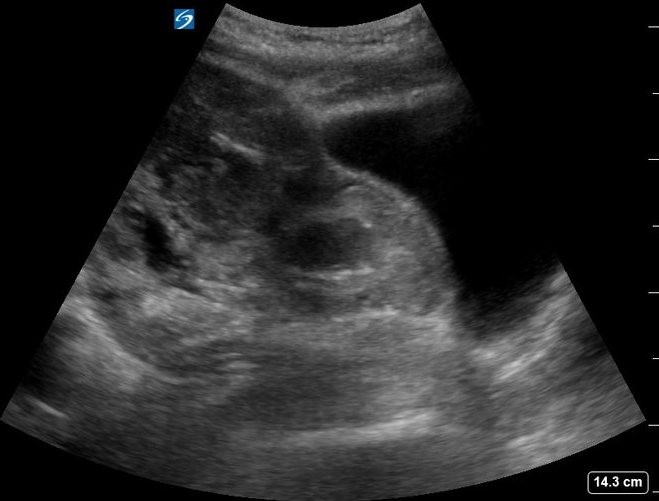

At the same time of the initial emergency physician evaluation, an ultrasound examination using a curvilinear transducer of the right upper quadrant revealed a large amount of intraperitoneal fluid (Figure 1, Video 1). The visualized uterine cavity was empty with mixed echogenicity surrounding the uterus. A bulging abnormality was noted in the anterior myometrium in the lower uterine segment, corresponding to the site of her prior Cesarean section (Figure 2). A gestational sac was visualized in the lower anterior uterine segment with a visible embryo and fetal heart movement. There was a thin amount of tissue between the sac and maternal bladder measuring 4.8 mm (Figure 3, Video 2).

Figure 1. Right upper quadrant ultrasound demonstrating large amount of free fluid.